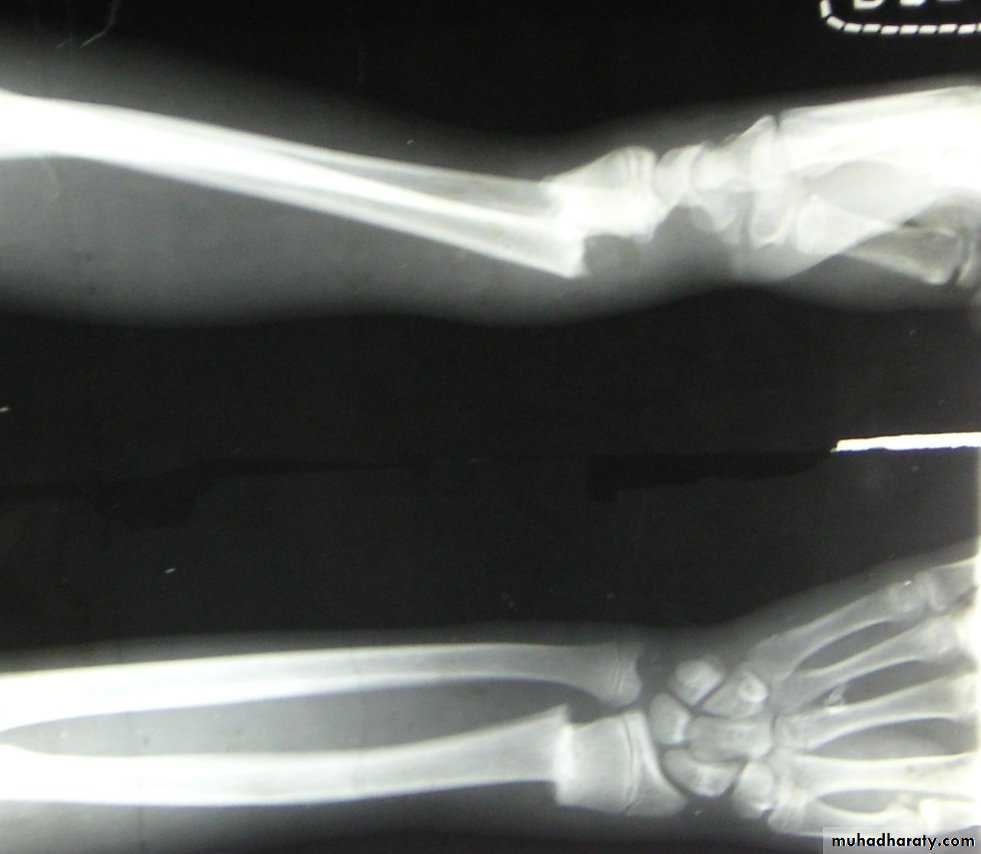

Slide 81- What we call this type of fracture ?.2- What is the suitable way of fixation ?.